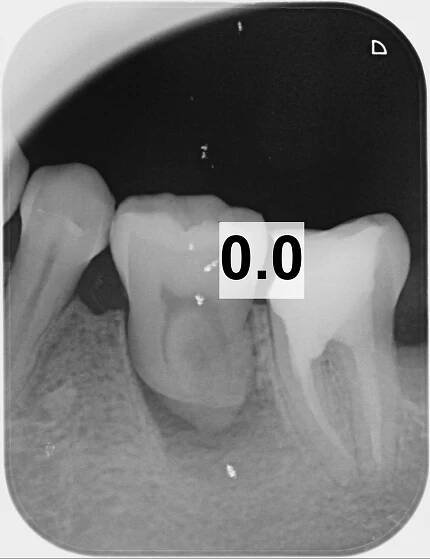

Resorptivní léze zubů koček | Moderní veterina na Praze 4 - Veterinární klinika Vethope